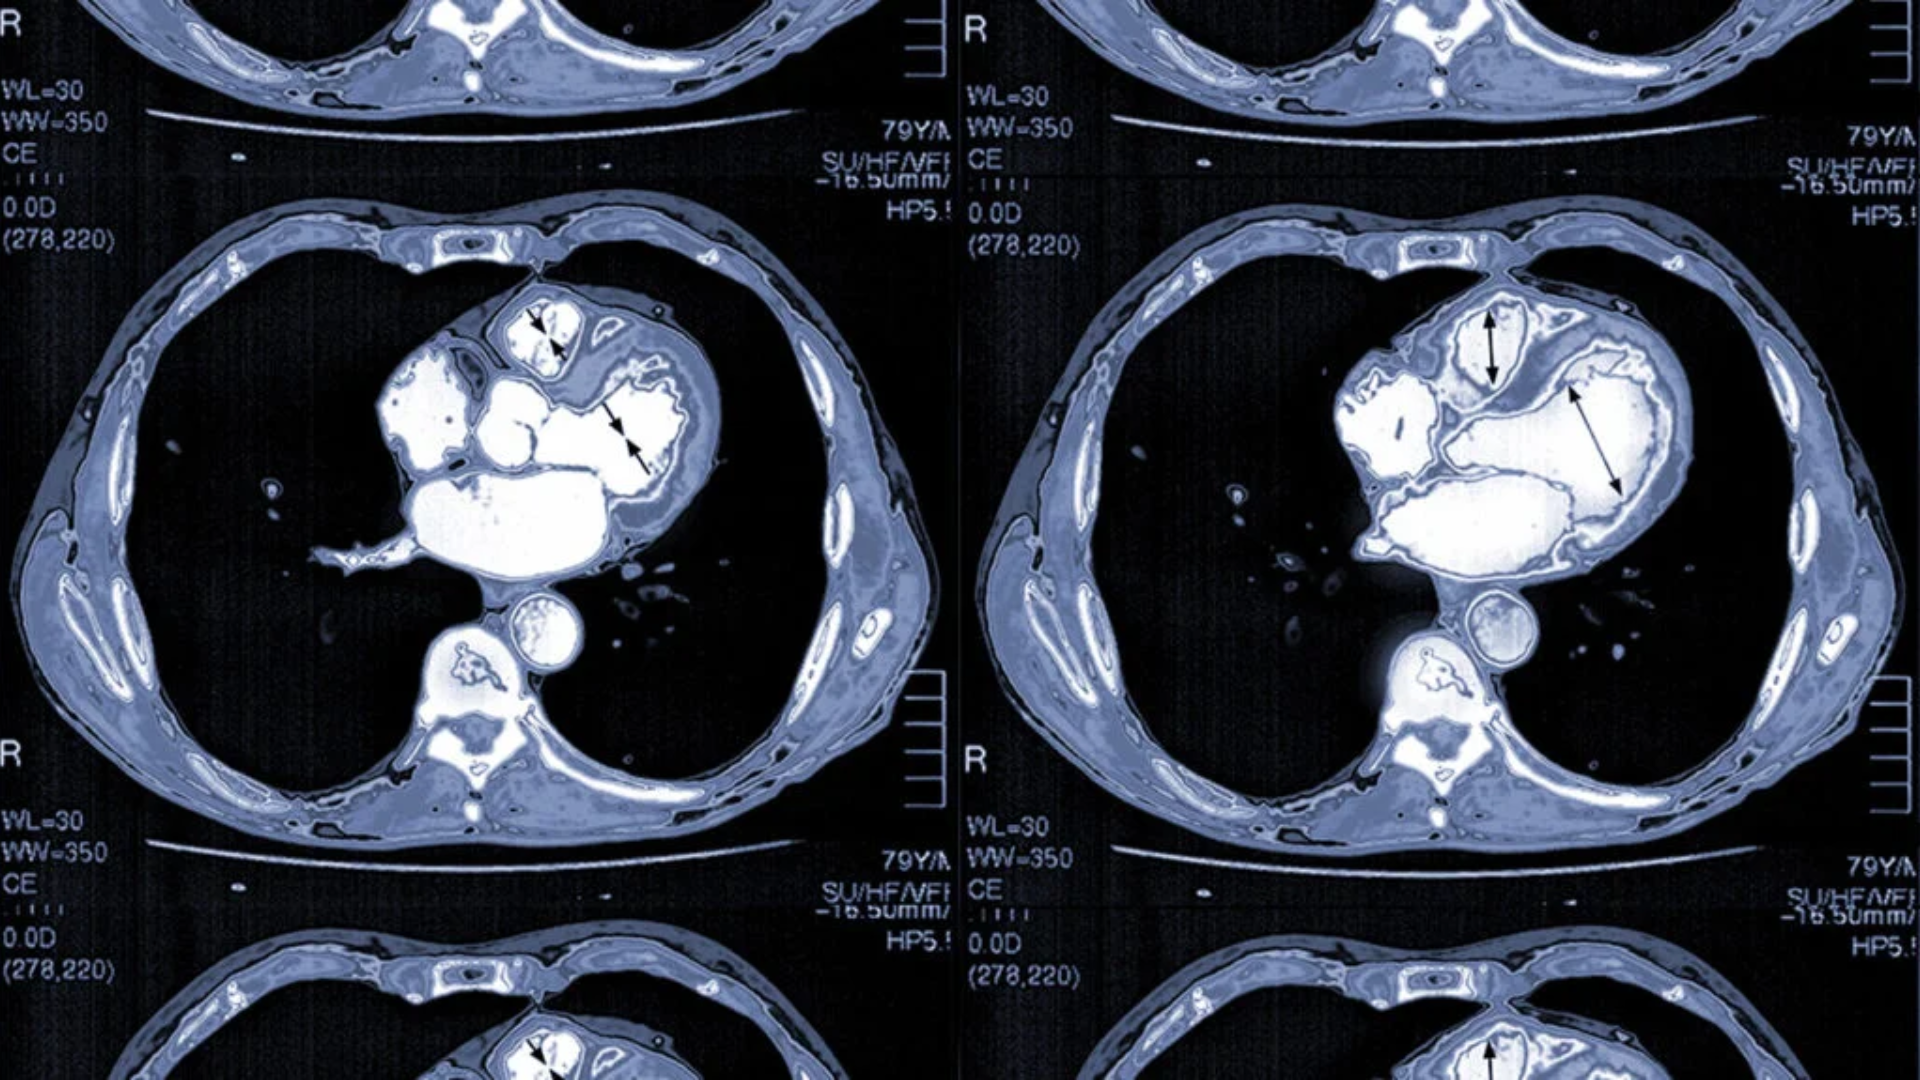

Chụp CT tim là kỹ thuật chẩn đoán hình ảnh sử dụng tia X kết hợp với hệ thống máy CT đa lát cắt để tạo ra hình ảnh chi tiết của tim và các cấu trúc liên quan như:

CT tim cho phép tái tạo hình ảnh tim theo nhiều mặt cắt và không gian ba chiều, giúp bác sĩ đánh giá chính xác cấu trúc giải phẫu và phát hiện nhiều bất thường tim mạch. CT tim là khái niệm rộng, trong đó CT mạch vành là một kỹ thuật chuyên sâu thuộc nhóm CT tim.